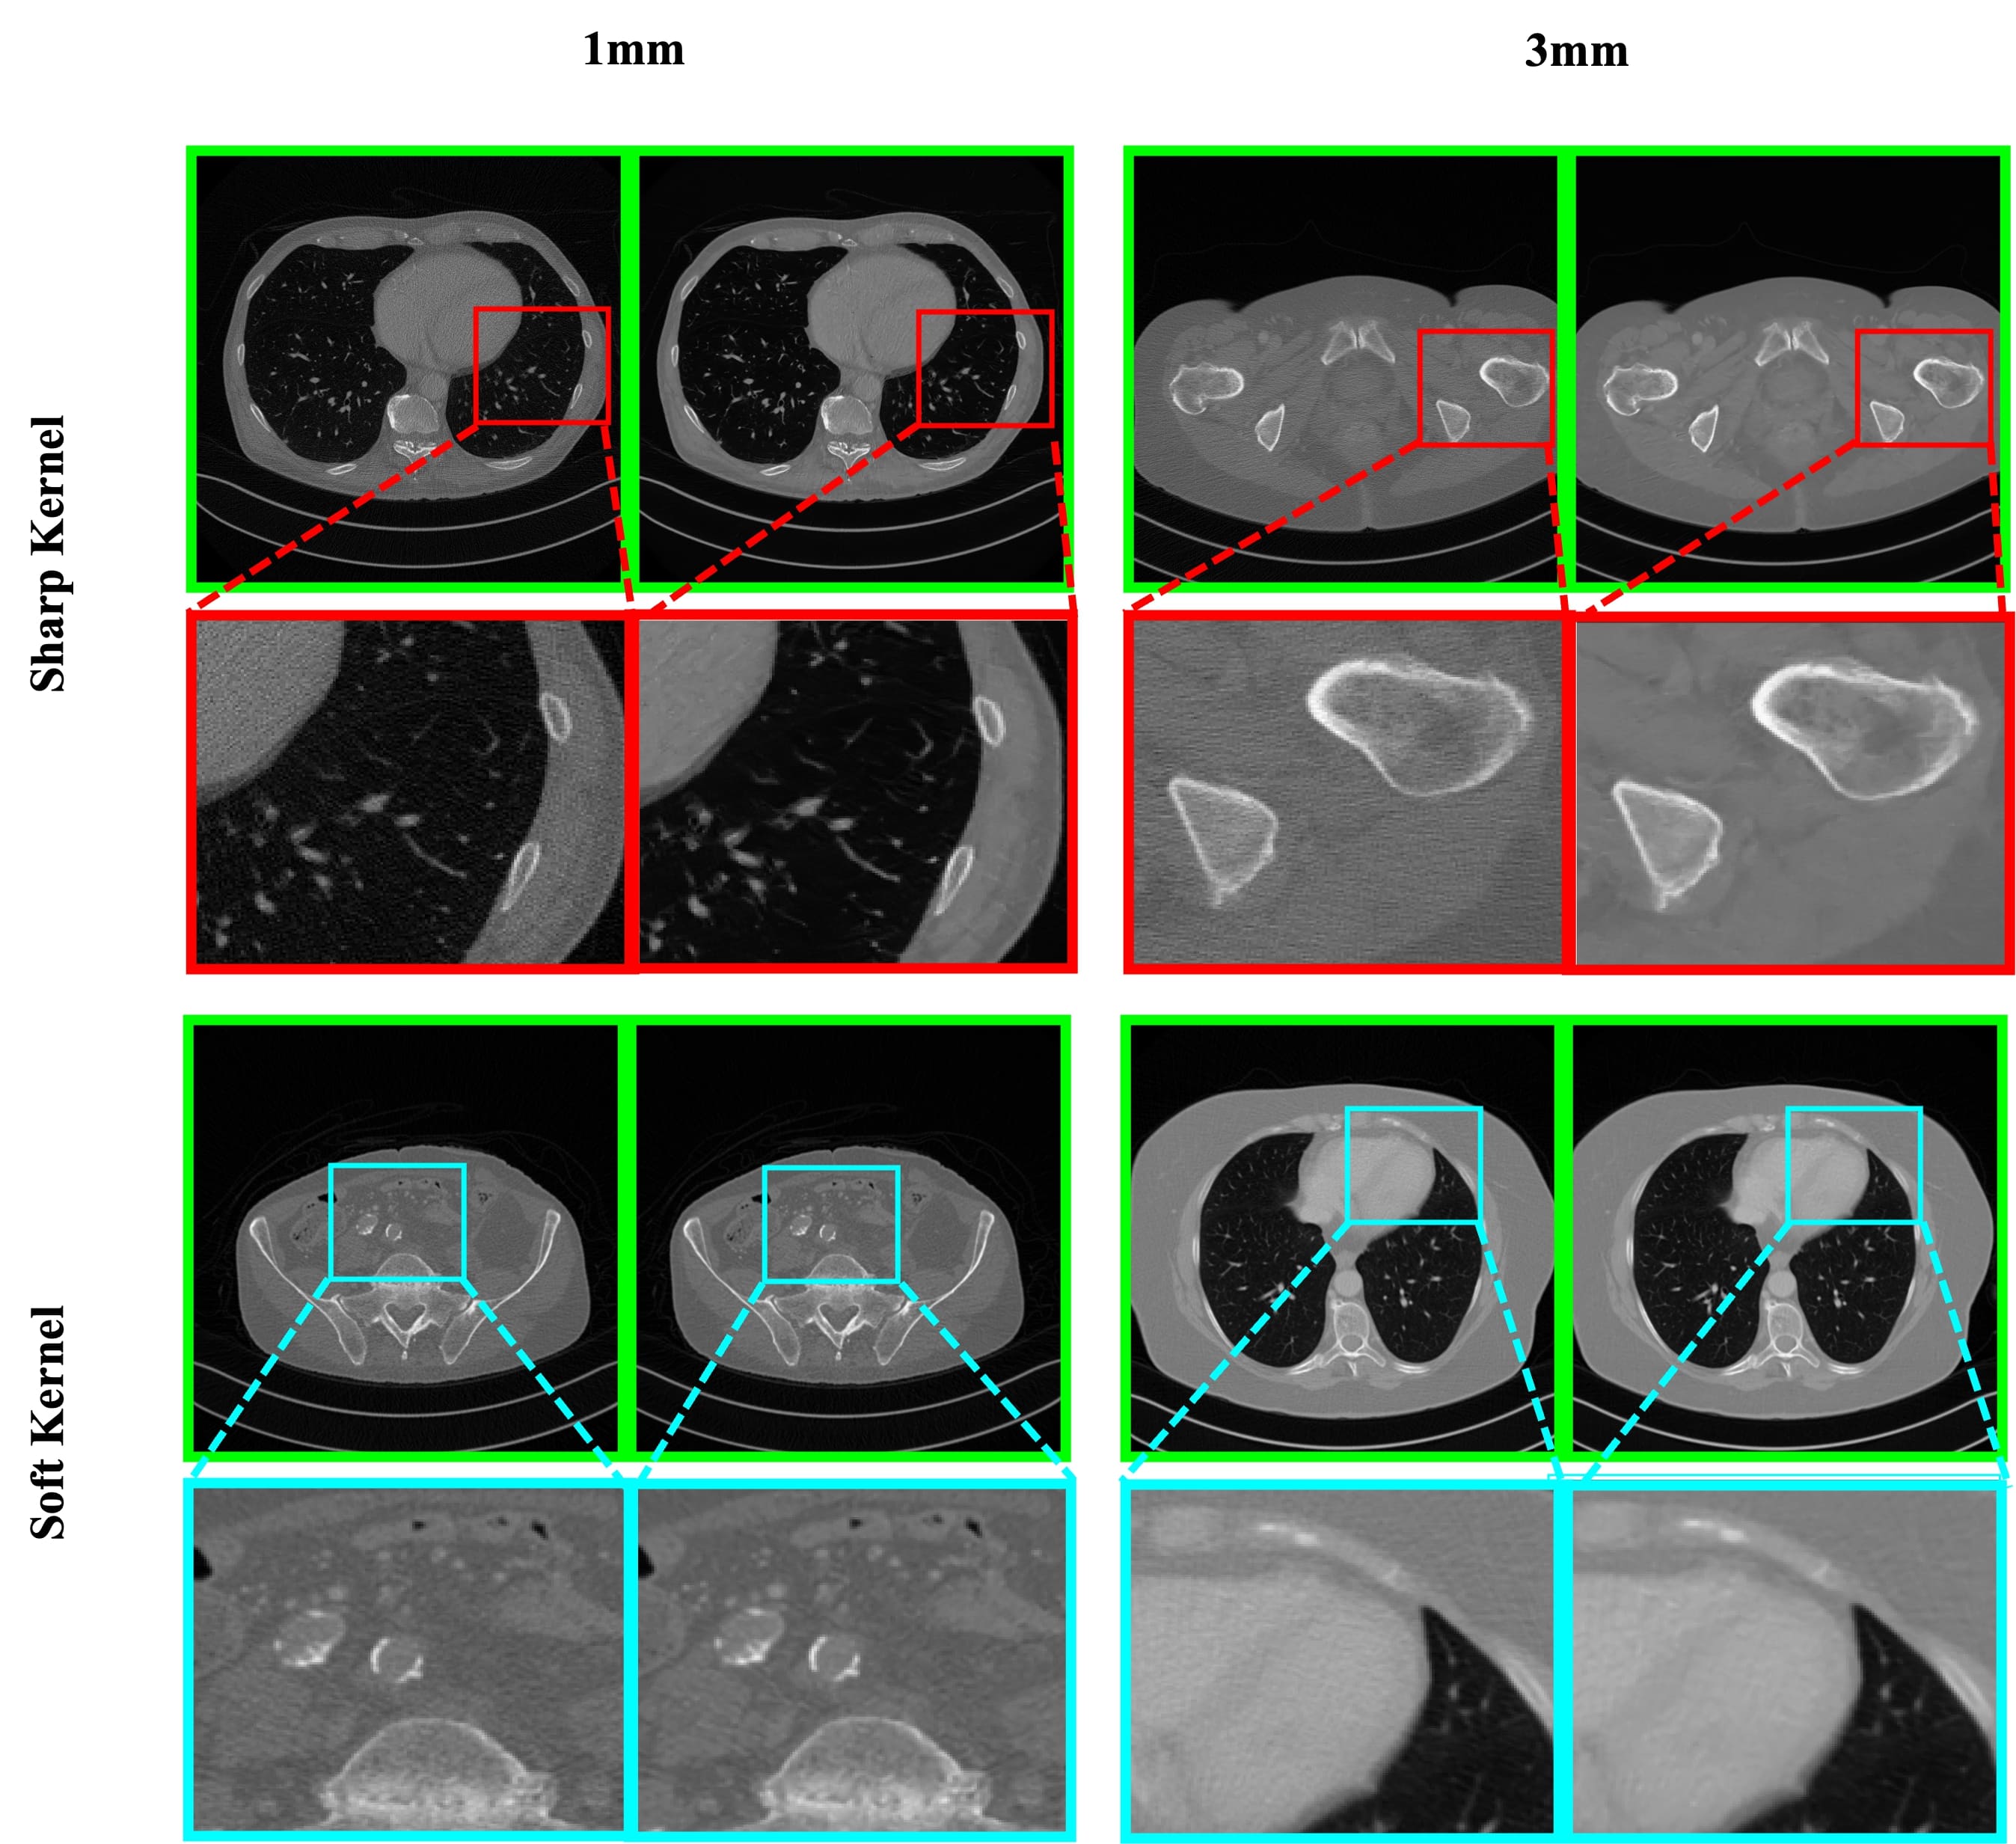

III-B Real-world Medical Image Denoising

Apart from the synthesized noisy images, we evaluated our method with real-world noisy CT images [51]. Therefore, the model is tuned to real-world noisy medical images. The proposed method has retrained leveraging transfer learning with low-dose sharp kernel CT images [3]. The trained model was evaluated with noisy CT images reconstructed with soft and sharp kernels, as shown in Fig. 11.

The visual results clarify that the proposed method can handle real-world noisy medical images. The proposed method can substantially reduce the low-dose CT noises without showing visual artifacts. In complex spatial regions, it also maintains salient information intact. Overall, the proposed method generates cleaner images and ensures plausible perceptual quality.

Refer to caption

Figure 11: Real-world low-dose CT image denoising with the proposed method. The proposed method can remove real-world noise without losing salient information. In each pair, left: low-dose noisy CT image and right: denoised image.